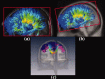

The function of the corpus callosum (CC) is to distribute perceptual, motor, cognitive, learned, and voluntary information between the two hemispheres of the brain. Accurate parcellation of the CC according to fiber composition and fiber connection is of upmost important. In this work, population-based probabilistic connection topographies of the CC, in the standard Montreal Neurological Institute (MNI) space, are estimated by incorporating anatomical cytoarchitectural parcellation with high angular resolution diffusion imaging (HARDI) tractography. First, callosal fibers are extracted using multiple fiber assignment by continuous tracking algorithm based on q-ball imaging (QBI), on 12 healthy and young subjects. Then, the fiber tracts are aligned in the standard MNI coordinate system based on a tract-based transformation scheme. Next, twenty-eight Brodmann's areas on the surface of cortical cortex are registered to the MNI space to parcellate the aligned callosal fibers. Finally, the population-based topological subdivisions of the midsagittal CC to each cortical target are then mapped. And the resulting subdivisions of the CC that connect to the frontal and somatosensory associated cortex are also showed. To our knowledge, it is the first topographic subdivisions of the CC done using HARDI tractography and cytoarchitectonic information. In conclusion, this sophisticated topography of the CC may serve as a landmark to further understand the correlations between the CC, brain intercommunication, and functional cytoarchitectures.